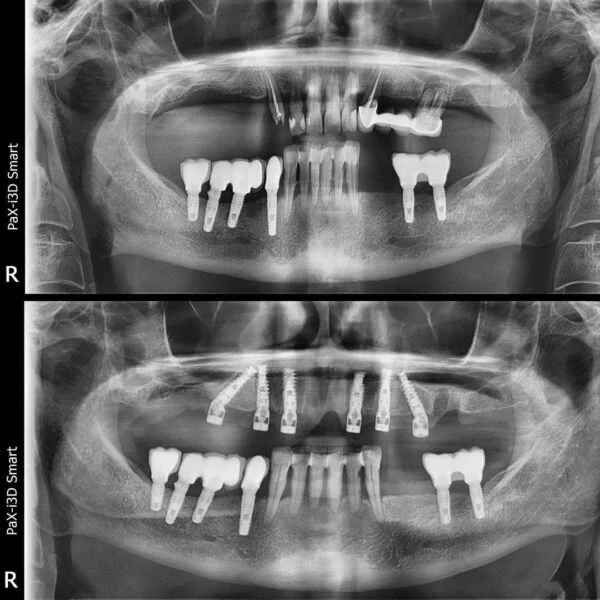

Implantul dentar este adesea recomandat deoarece prezintă foarte multe avantaje, iar, de multe ori, este unica soluție pentru protezarea unei edentații.